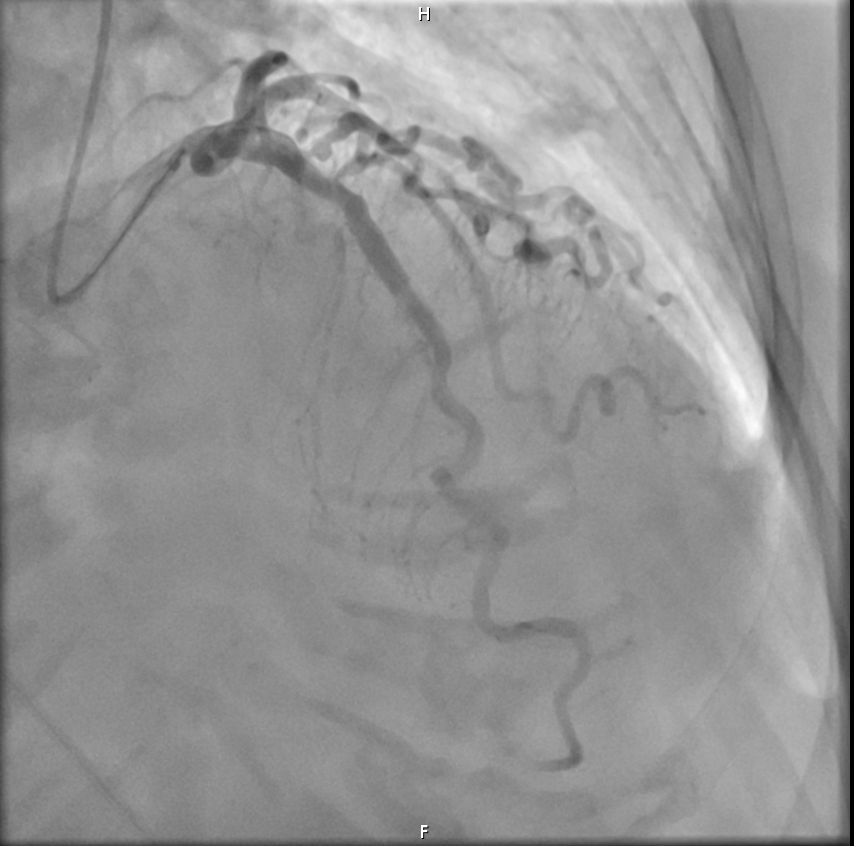

En la sala de hemodinámica se realiza en primer lugar cateterismo coronario hallándose estenosis de 70% del segmento medio de la arteria coronaria Descendente Anterior (DA). A través de Intervención Coronaria Percutánea se implanta stent farmacoactivo con buen resultado final.

Síndrome de Tako-Tsubo activado como código IAM + Enfermedad coronaria de 1 vaso: descendente anterior media (70%).